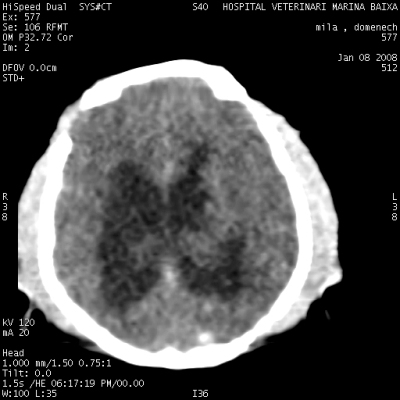

La tomografía computerizada o TAC es un método de diagnóstico por imagen . En ocasiones la radiografía , la ecografía y la endoscopia no son suficientes para poder realizar un diagnóstico preciso. La TAC y la RMN son técnicas mas avanzadas de diagnóstico. Las principales aplicaciones del TAC son en neurología , oncología ( cáncer ) y traumatología , pero también para diagnosticar patologías torácicas , abdominales y cardiovasculares . Para el diagnóstico y tratamiento del cáncer en perros y gatos la TAC juega un papel fundamental , facilitando la localización del tumor, detección de metástasis , plan prequirúrgico y seguimiento de la enfermedad.

Cerebro y cráneo: